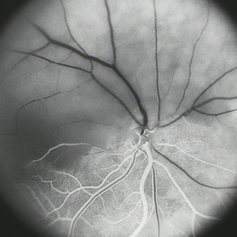

Hemi-CRAO

Mid-phase (laminar venous return) fluorescein angiogram image of an embolic superior hemi-CRAO showing marked delay in filling of the superior retinal arteriolar and venous vasculature and total loss of the retinal capillary bed in the superior hemisphere OD.

Condition/keywords: capillary closure, capillary nonperfusion, central retinal artery occlusion (CRAO), FA mid phase, fluorescein angiogram (FA)